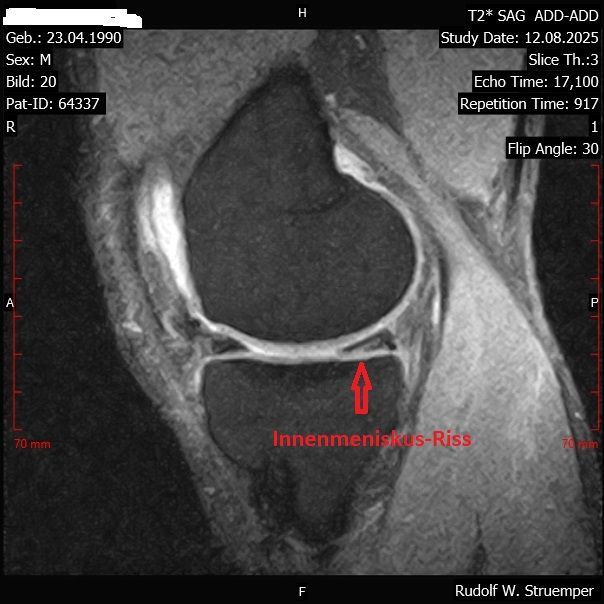

Meniskus-Riss - vor- und nach der Behandlung mit Fibrinkleber und ACS

Die Gewebe-Klebungen erfolgen ohne Operation in örtlicher Betäubung unter Kernspin-Kontrolle mit einem Fibrin-Kleber (Tisseel) und anschließend wird die Heilung durch Injektionen von Wachstumsfaktoren (ACS) gefördert. Seit August 2016 haben wir mit dieser von uns entwickelten neuen Methode über 1090 Behandlungen durchgeführt.